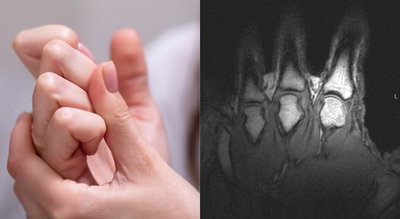

Researchers now agree that the sound produced when knuckles, toes or other joints crack is caused by gas, not bones grinding or cartilage snapping. A widely cited2015 studyused real-time MRI imaging to observe joints as they cracked, capturing the process as it happened rather than relying on theory alone.

The scans showed that when a joint is pulled or stretched, the pressure inside the joint space drops suddenly. Synovial fluid, the slippery liquid that lubricates joints, cannot fill the increasing space quickly enough. As a result, a gas-filled cavity forms inside the fluid. This process is known as tribonucleation, and the rapid formation of that cavity is what produces the distinctive popping sound.

Side by side MRIs revealing a gas bubble forming as joints in the fingers are cracked (University of Alberta)

Greg Kawchuk, a professor in the Faculty of Rehabilitation Medicine at the University of Alberta, described the process in simple terms while speaking to Science Alert.“When you do that, you can actually see very clearly what is happening inside the joints,” he said.“It’s a little bit like forming a vacuum. As the joint surfaces suddenly separate, there is no more fluid available to fill the increasing joint volume, so a cavity is created and that event is what’s associated with the sound.”This finding overturned earlier theories from the 1970s that suggested the noise came from gas bubbles collapsing rather than forming.